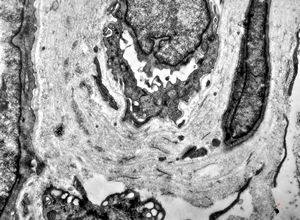

brain vessel - CADASIL - arrows:granular osmiophilic material (GOM)between basement membranes

brain vessel - CADASIL - arrow:granular osmiophilic material (GOM)in basement membrane